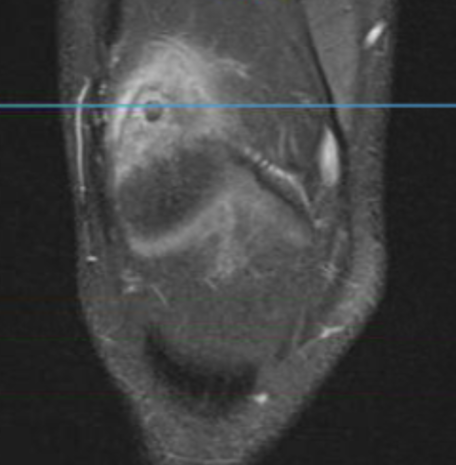

MRI

Osteoid osteoma tibia

Osteoid osteoma femur